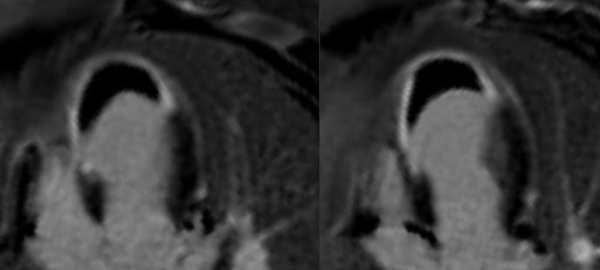

Case 226: Diagnosing Left Ventricular Free Wall Rupture without Aneurysm

Diagnosing ventricular free wall rupture is not difficult, though these patients rarely come for cardiac MRI, since they are usually serious and clinically unstable.